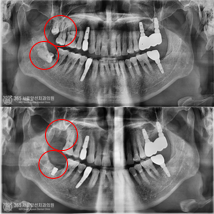

완전매복사랑니 발치와 임플란트 수술을 한 번에 치료한 환자분

안녕하세요. 주안동치과 365서울앞선치과의원입니다.오늘은 완전매복 사랑니 발치와 임플란트 수술을 한 번..